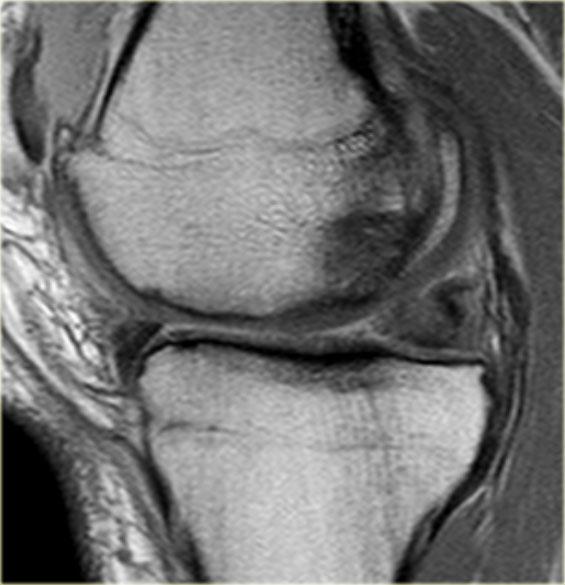

Hãy quan sát hình ảnh bên trái và cố gắng xác định vấn đề của sụn chêm này là gì.

Sau đó tiếp tục xem các hình ảnh liên tiếp tiếp theo của cùng bệnh nhân này.

Như bạn đã đoán được qua tiêu đề của đoạn này, đây là một trường hợp sụn chêm lật (flipped meniscus).

Sụn chêm lật là một dạng đặc biệt của rách dạng quai xô (bucket-handle tear).

Sụn chêm lật xảy ra khi mảnh vỡ của sừng sau bị lật ra phía trước, khiến sừng trước của sụn chêm có vẻ to hơn bình thường.